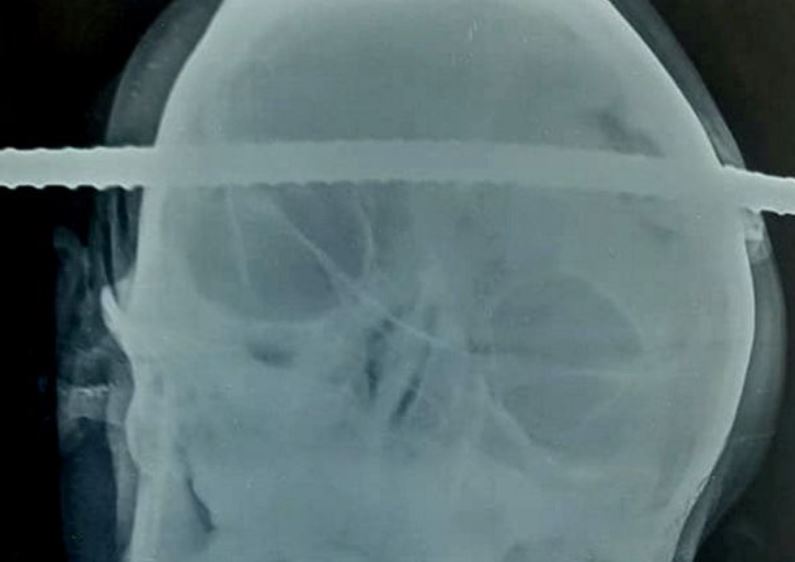

El hecho ocurrió en Balaghat, India, cuando Sanjay Bache estaba realizando labores en la obra, pero cayó a un pozo y una barra de metal le perforó el cráneo.

Según informa The Mirror, el joven fue trasladado rápidamente a un hospital y los médicos determinaron que el elemento perforó la región temporal derecha y la frontal izquierda del cerebro.

Un equipo de neurocirujanos, en una operación de 90 minutos, logró extraer la barra sin problemas.

Uno de los especialistas, Pramod Giri, sostuvo que los canales que conducen sangre al cerebro estuvieron a milímetros de ser afectados. “Realicé la cirugía con toda precaución para que no se produzcan daños en las estructuras circundantes", explicó.